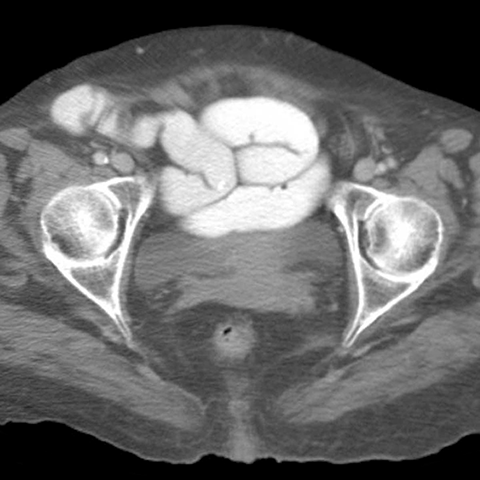

77 year-old woman presents with abdominal pain,vomiting, fever, and tachycardia [1 of 3]